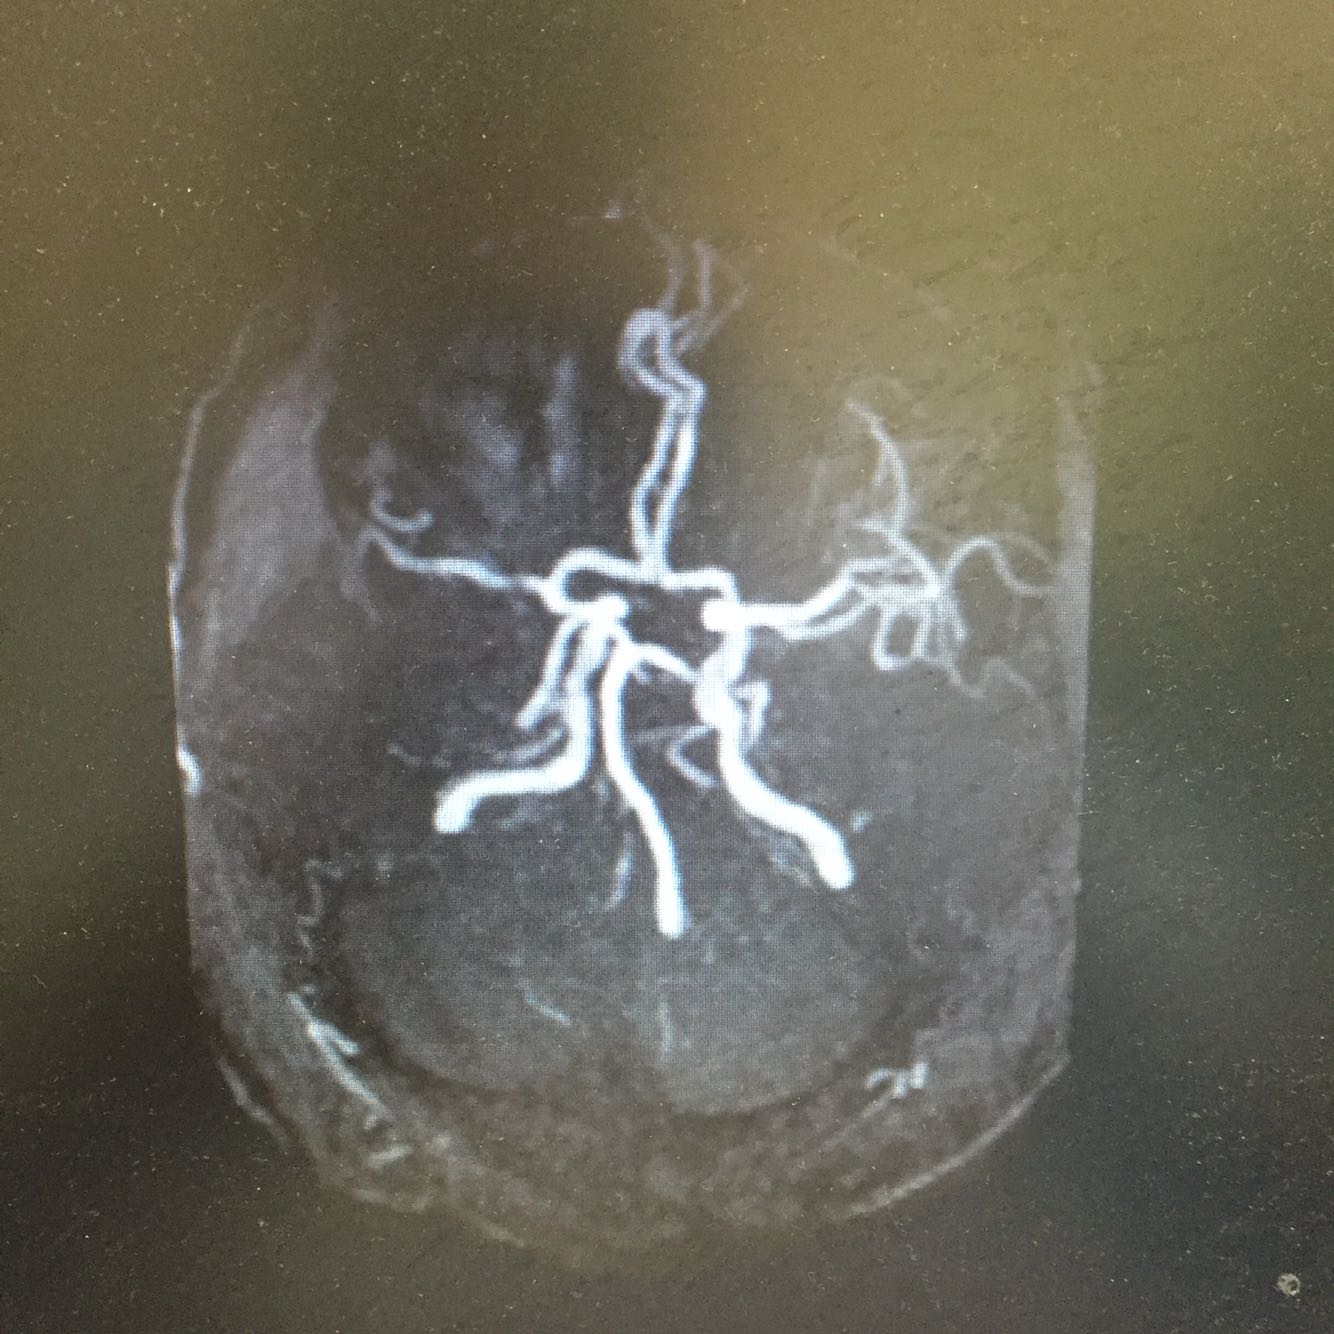

查体:血压110/70mmHg 神志清楚,言语欠流利,查体合作,双侧瞳孔等大同圆,对光反射存在,双眼活动自如,左侧鼻唇沟浅,伸舌居中,左侧肢体肌力4级,右侧肌力5级,肌张力正常,腱反射对称,双侧感觉对称,双下肢Babinski(+)Chaddock(+),颈强(-),克氏征(-) 头DWI示:左侧侧脑室后脚新发梗死。颅内多发占位性病灶,考虑转移瘤